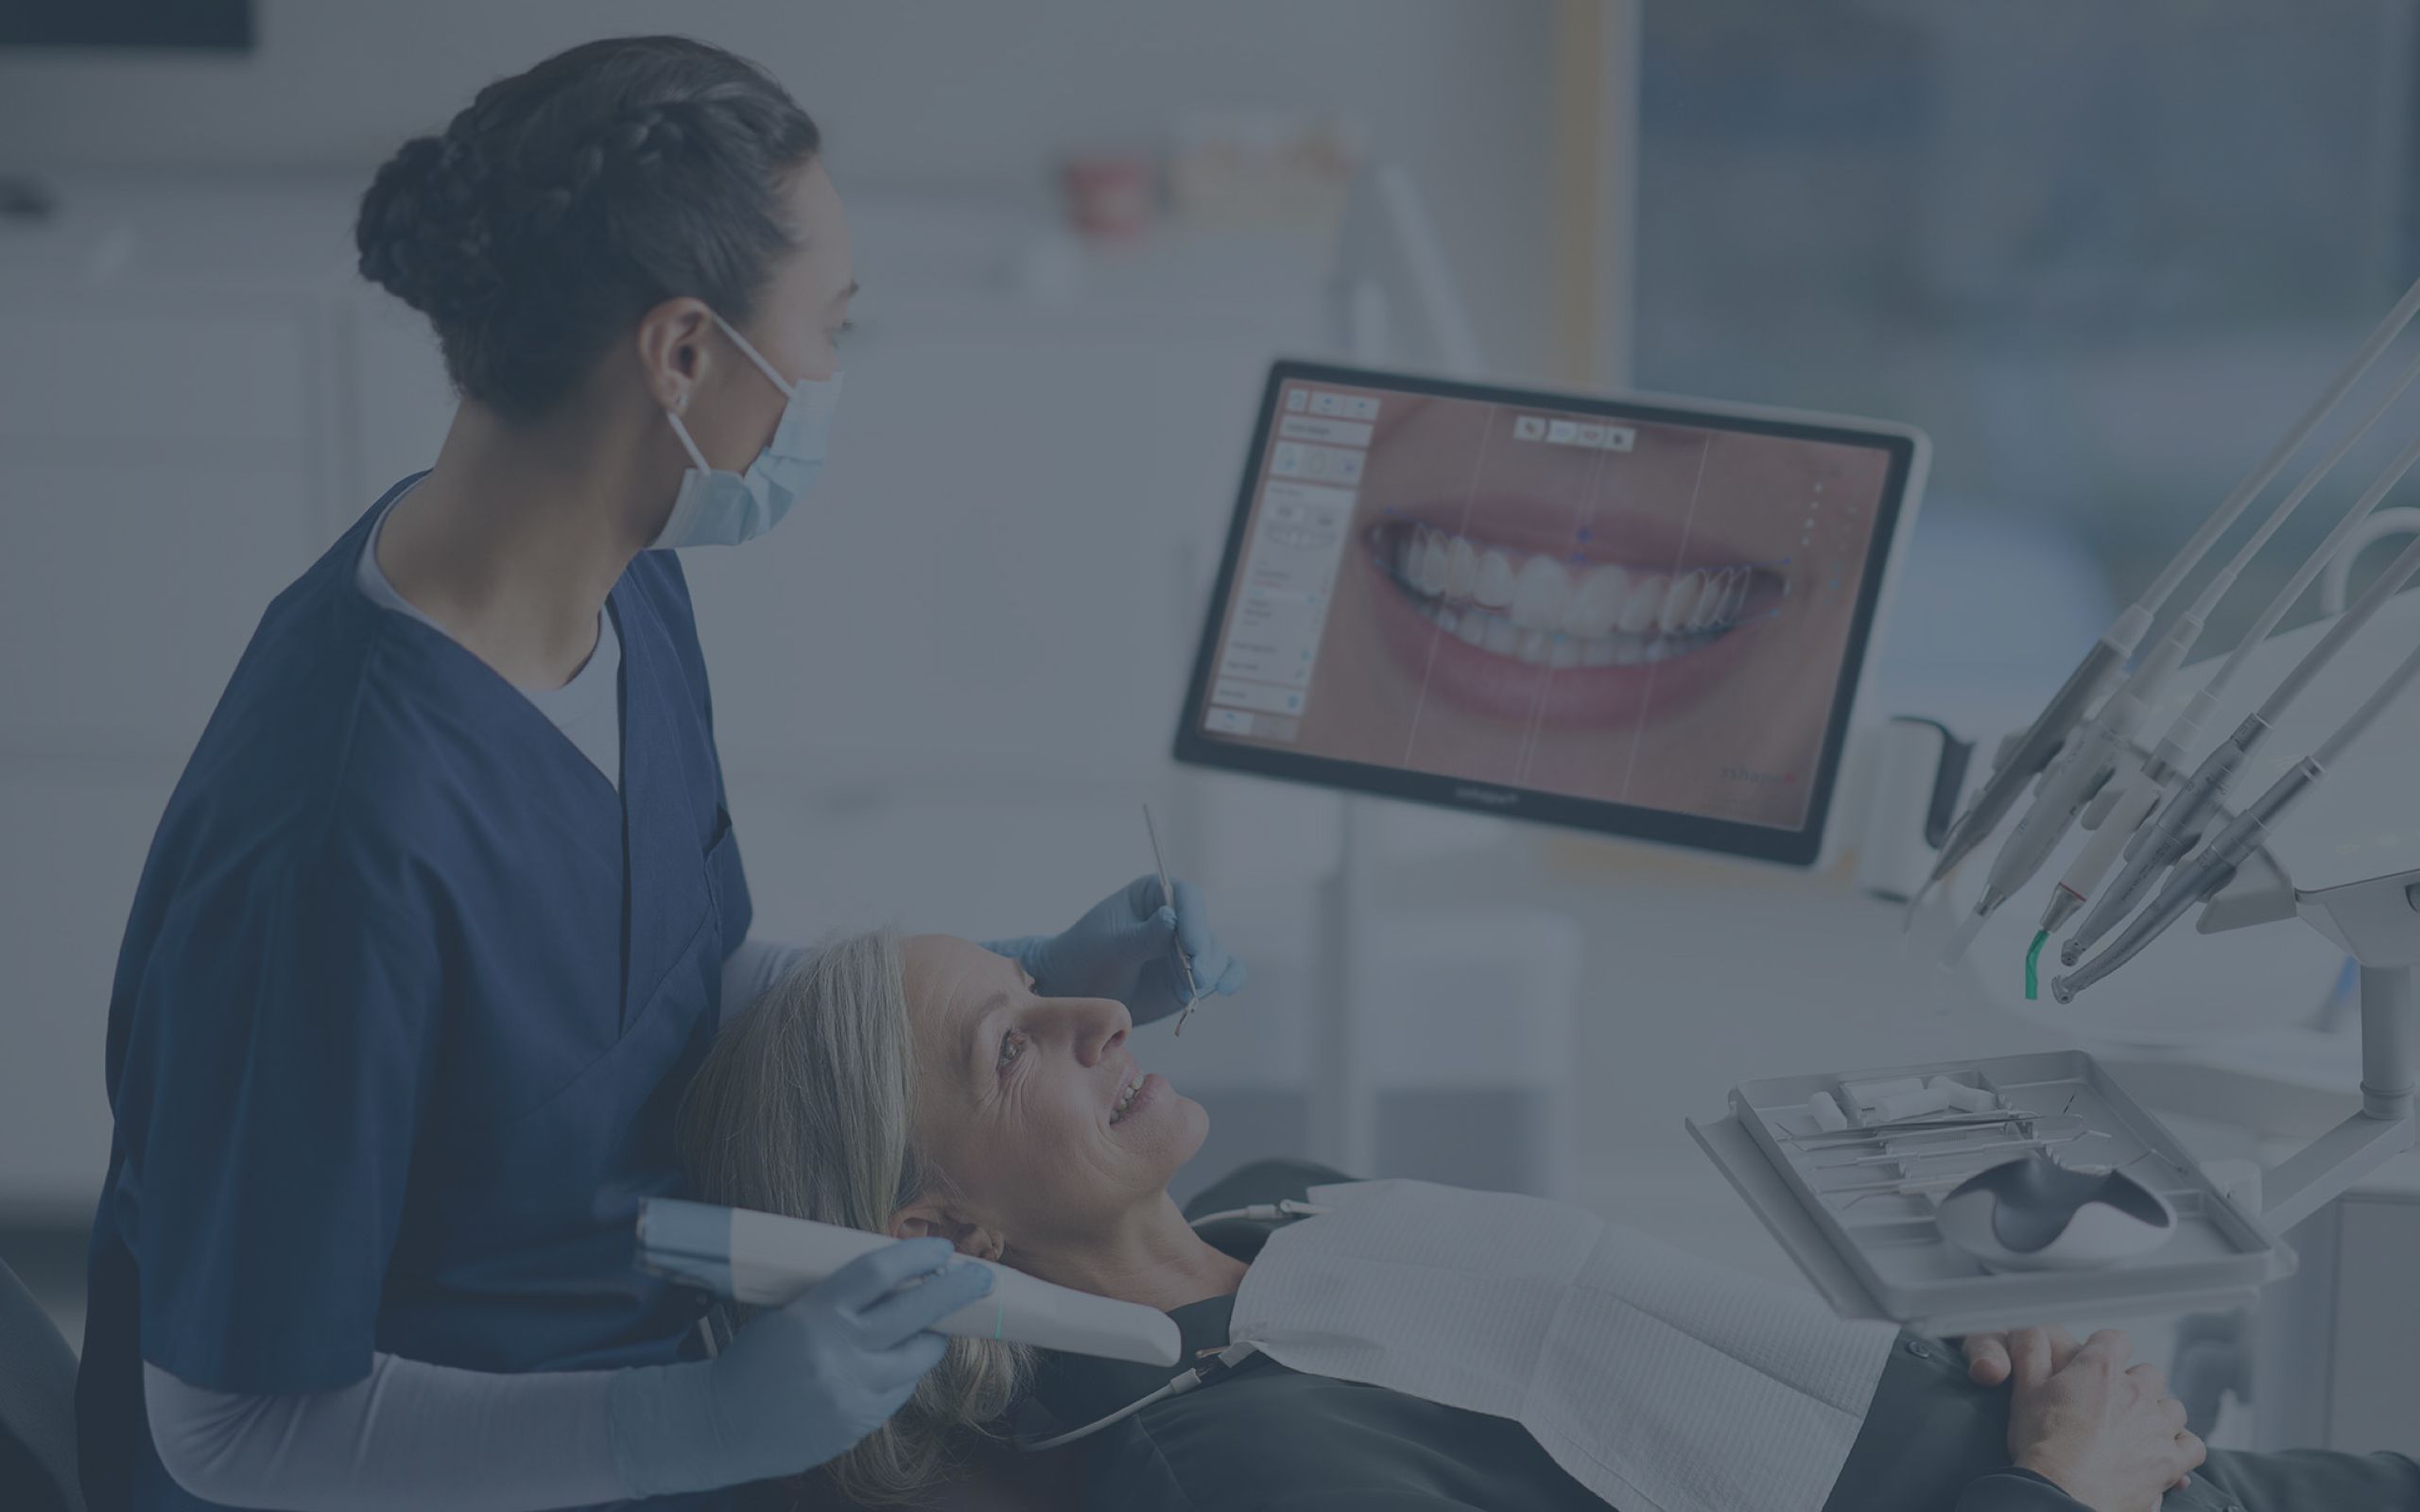

3shape Smile Design

Immerse yourself in the artistic beauty of 3shape Smile Design through substantial collections of inspiring images. blending traditional techniques with contemporary artistic interpretation. transforming ordinary subjects into extraordinary visual experiences. The 3shape Smile Design collection maintains consistent quality standards across all images. Ideal for artistic projects, creative designs, digital art, and innovative visual expressions All 3shape Smile Design images are available in high resolution with professional-grade quality, optimized for both digital and print applications, and include comprehensive metadata for easy organization and usage. Our 3shape Smile Design collection inspires creativity through unique compositions and artistic perspectives. Instant download capabilities enable immediate access to chosen 3shape Smile Design images. Our 3shape Smile Design database continuously expands with fresh, relevant content from skilled photographers. The 3shape Smile Design collection represents years of careful curation and professional standards. Diverse style options within the 3shape Smile Design collection suit various aesthetic preferences. Multiple resolution options ensure optimal performance across different platforms and applications. Professional licensing options accommodate both commercial and educational usage requirements. Each image in our 3shape Smile Design gallery undergoes rigorous quality assessment before inclusion. Time-saving browsing features help users locate ideal 3shape Smile Design images quickly. Advanced search capabilities make finding the perfect 3shape Smile Design image effortless and efficient.